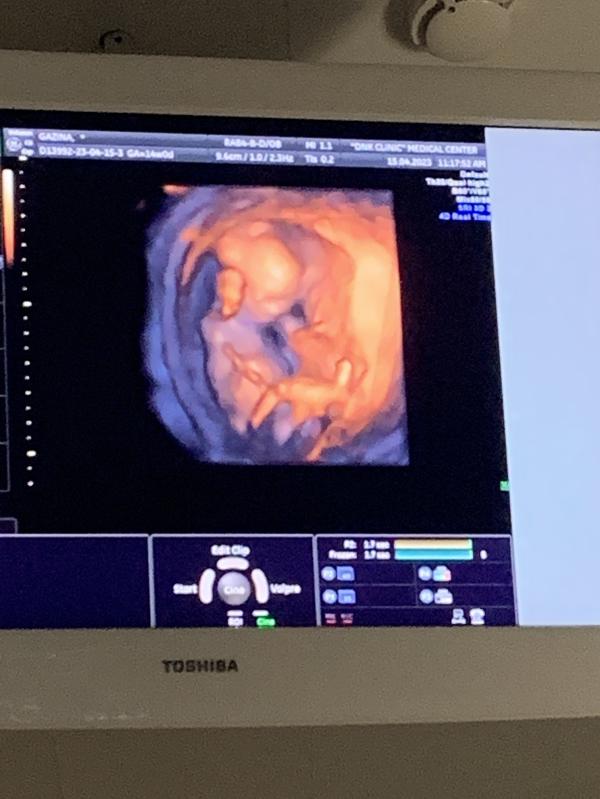

Сходила я все таки перепроверить 1 скрининг в платную поликлинику 😀

Всё хорошо 👌 как и должно быть, пол даже не спрашивала , нам малыш решил сам показать своё добро😄. И вот в 14 недель мы знаем кто у нас будет))